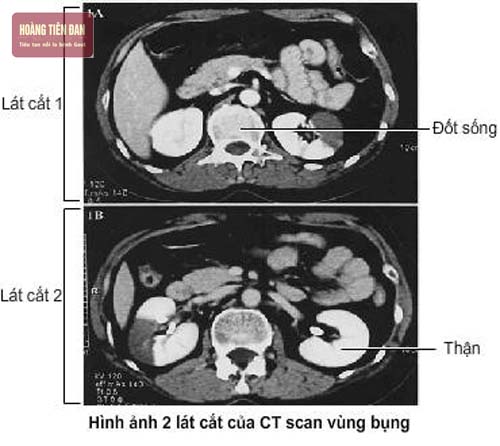

Hiện nay có rất nhiều cách để chẩn đoán sỏi thận nhưng chủ yếu nhất vẫn là chẩn đoán lâm sàng, chẩn đoán qua siêu âm, chụp X quang và xét nghiệm. Dựa vào đó giúp cho việc điều trị bệnh kịp thời, ngăn chặn được các biến chứng nguy hiểm do bệnh gây ra.